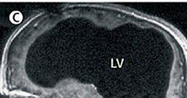

光片显示,该男子75%的脑组织已消失不见。

中新网8月18日电 据英国媒体报道,法国一名男子曾因腿部疼痛去医院检查,医生却找不出病根。在对其进行了全身体检后才发现,原来这名男子的腿疼是由脑部病变引起的,而该男子的大脑只剩下正常人大脑体积的一半都不到了。

报道称,这件事其实发生在2007年,近日由著名医学杂志《柳叶刀》披露。这名大脑神秘消失的男子当年44岁,医生在对其进行脑部检查后发现,他左右半脑上的额叶、顶叶、颞叶及枕叶都萎缩了。

在对这名男子的病史进行详细调查后发现,原来他童年时患有后天脑积水症。但在他14岁时,经历了分流术,随后的30年,这名男子和家人都以为完全康复了。但其实他的大脑还是在病变,最终,脑内的积水损坏了脑组织,导致其大脑50%至75%的部分都消失了。